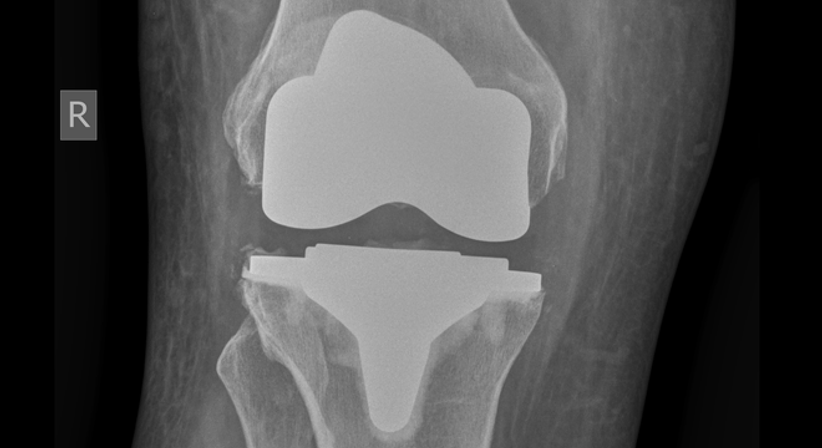

Totalendoprothese (Knie-TEP)

Eine Totalendoprothese des Knies, auch als Knie-TEP abgekürzt, ist ein chirurgischer Eingriff, bei dem das gesamte Kniegelenk durch eine künstliche Prothese ersetzt wird. Die Prothese besteht aus Metall und Kunststoff und ahmt die natürliche Struktur und Funktion des Kniegelenks nach.